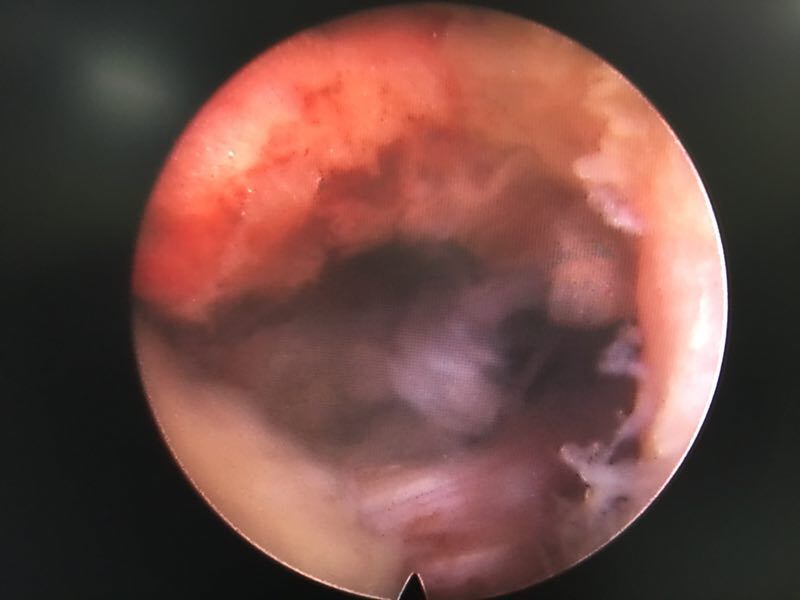

椎间孔镜下腰5骶1椎板间隙入路髓核摘除术

诊断:腰5骶1椎间盘突出症 治疗方案:椎间孔镜下经椎板间入路髓核摘除术

术后患者疼痛完全消失